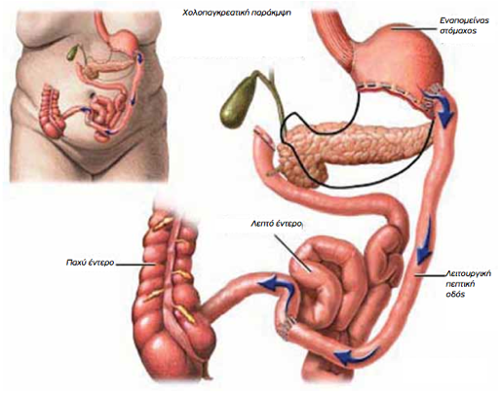

Χολοπαγκρεατική παράκαμψη

Χολοπαγκρεατική παράκαμψη

Η λογική αυτής της επέμβασης είναι αφενός μεν η μείωση του μεγέθους του στομάχου, αφετέρου δε η εκτροπή των εκκρίσεων του παγκρέατος, του δωδεκαδακτύλου και του ήπατος χαμηλά στον τελικό ειλεό, οπότε η ανάμειξη με τις τροφές και η πέψη και απορρόφηση των θρεπτικών συστατικών γίνεται σε πολύ μικρό τμήμα εντέρου άρα είναι σαφώς μειωμένη.

Χολοπαγκρεατική παράκαμψη

Χολοπαγκρεατική παράκαμψηΗ λογική αυτής της επέμβασης είναι αφενός μεν η μείωση του μεγέθους του στομάχου, αφετέρου δε η εκτροπή των εκκρίσεων του παγκρέατος, του δωδεκαδακτύλου και του ήπατος χαμηλά στον τελικό ειλεό, οπότε η ανάμειξη με τις τροφές και η πέψη και απορρόφηση των θρεπτικών συστατικών γίνεται σε πολύ μικρό τμήμα εντέρου άρα είναι σαφώς μειωμένη.